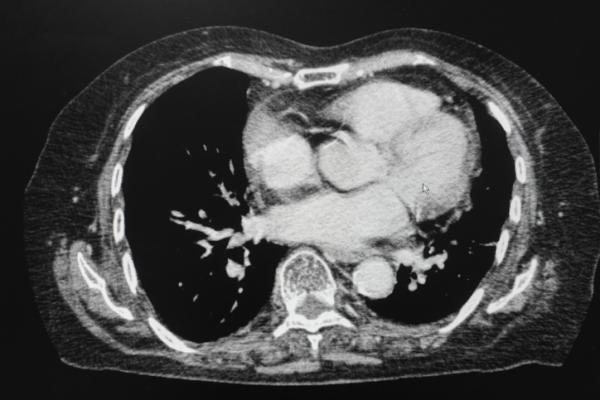

Under the current standard of care, patients referred for palliative radiation must undergo a CT simulation scan before they can receive treatment. CT simulation generates 3D images that are used by the patient’s care team to create a custom radiation treatment plan for the patient. This process usually takes several hours, even when using expedited workflows.

Yet many of these patients have also undergone a recent diagnostic CT scan, performed in medical imaging departments outside of the cancer center as a part of routine follow-up or other care. Previous research found that radiation oncology teams could produce clinically acceptable palliative treatment plans for patients with bony and soft tissue metastases using these existing diagnostic CT scans, rather than the more time-intensive simulation scans. In the current study, O’Neil and her colleagues investigated whether using existing CT scans to plan treatment ahead of a patient’s arrival could reduce their time at the cancer center while still delivering appropriate care.

Thirty-three patients needing palliative radiation for tumors in their thoracic, abdominal, pelvic or proximal limb areas were randomized to either standard treatment planning with on-site CT simulation scans, or to treatment planned before their appointment using diagnostic CT scans taken up to 28 days prior.